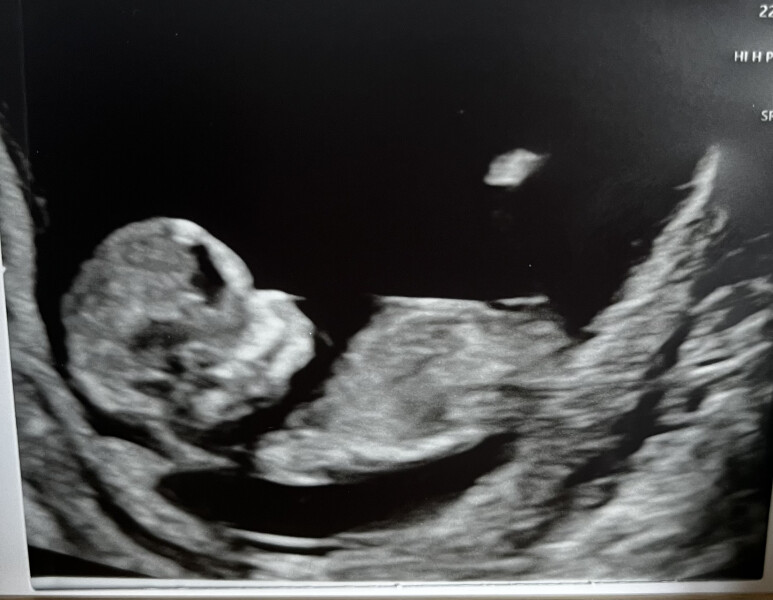

@lovesT @F03t @tasha4eva10 lovely scans!!

I'm finally brave enough to return to this thread after having our 12 week scan yesterday! Saw the little one's heartbeats 💓